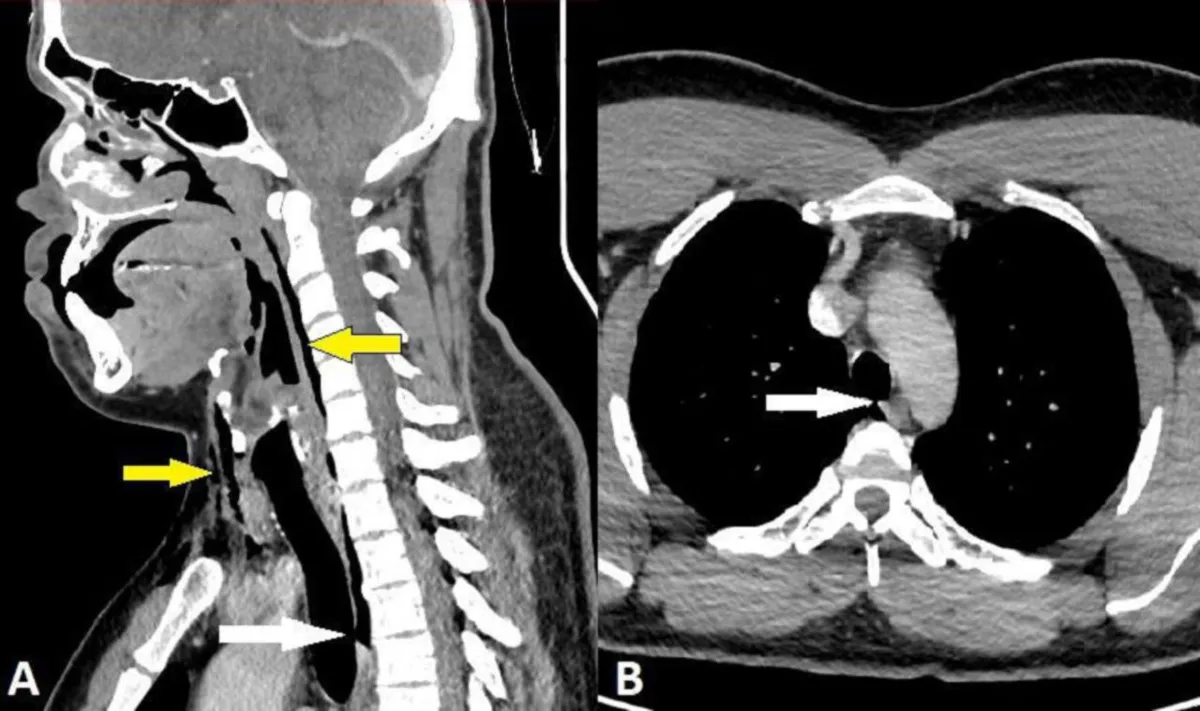

O paciente relatou fortes dores no pescoço imediatamente após segurar um espirro enquanto dirigia. Com rinite alérgica, ele procurou ajuda médica e foi submetido a uma tomografia computadorizada, revelando uma ruptura na traqueia com pneumomediastino, presença de ar entre os pulmões.

Cinco semanas após o incidente, uma nova tomografia computadorizada revelou a completa resolução do problema, sem qualquer anormalidade na traqueia. O paciente, no entanto, foi orientado a evitar atividades físicas intensas e a não segurar espirros por duas semanas, indicando a importância de precauções após o episódio incomum.